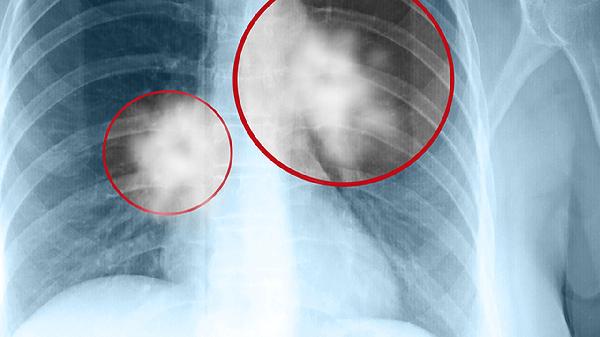

对于多数实体肿瘤中晚期患者,单纯药物治疗难以彻底清除肿瘤。肿瘤异质性导致部分细胞对药物产生耐药,影响治疗效果。肿瘤微环境形成物理屏障阻碍药物渗透,降低药效。某些低分化肿瘤对现有药物敏感性差,治疗效果有限。多发转移病灶使药物难以全面覆盖,存在治疗盲区。肿瘤干细胞的存在可能导致治疗后复发,需配合其他治疗手段。